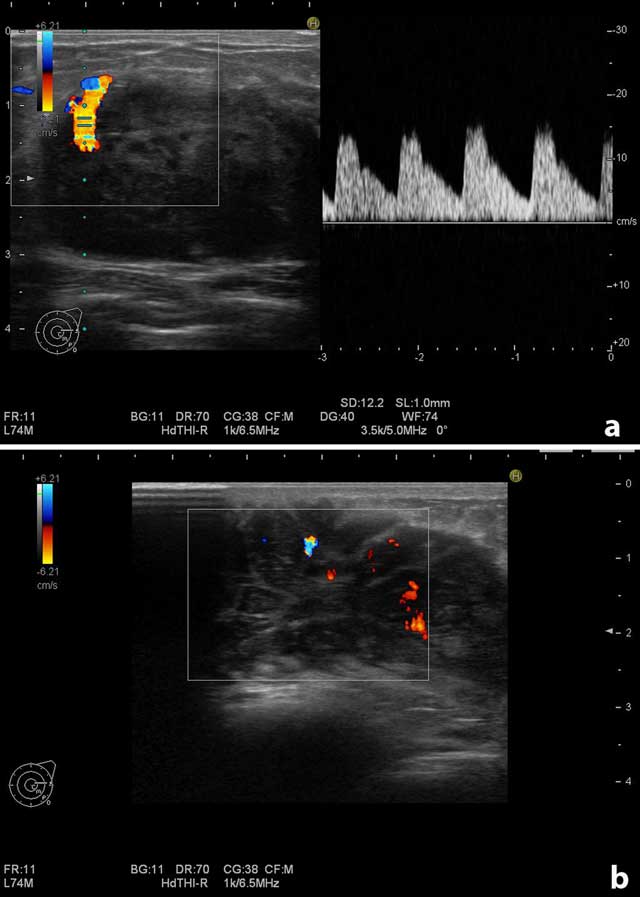

Figure 2

Doppler examination of the largest mass on the right breast. (a) Increased vascularity at the contours of the mass. (b) Increased vascularity in the internal part of the mass.